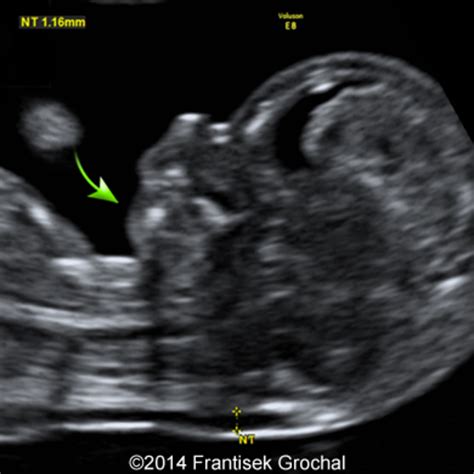

During the first and second trimesters, doctors look for specific anatomical findings. The most well-known screening takes place between 11 and 14 weeks of gestation, known as the Nuchal Translucency (NT) scan. Here are some of the markers that clinicians pay close attention to:

• Nuchal Translucency: This refers to the fluid-filled space at the back of the baby's neck. A thickened NT measurement can be an indicator of potential genetic issues.

• down syndrome ultrasound 12 weeks